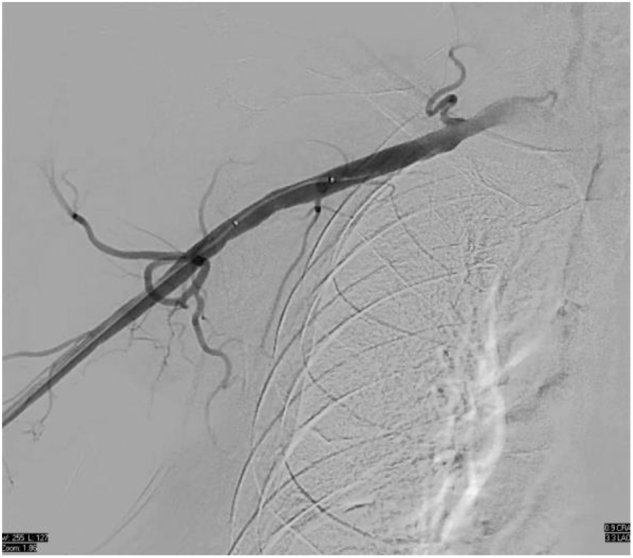

Case presentation: We present the case of a 68-year-old male with severe multivessel coronary artery disease with reduced left ventricular ejection fraction, and bilateral iliofemoral artery disease. Since there was difficulty in accessing the femoral arteries, axillary artery access was used to insert an Impella CP device to support high-risk PCI. The procedure involved successful revascularization of complex lesions using rotational atherectomy and stenting. The patient remained hemodynamically stable throughout and recovered without complications.